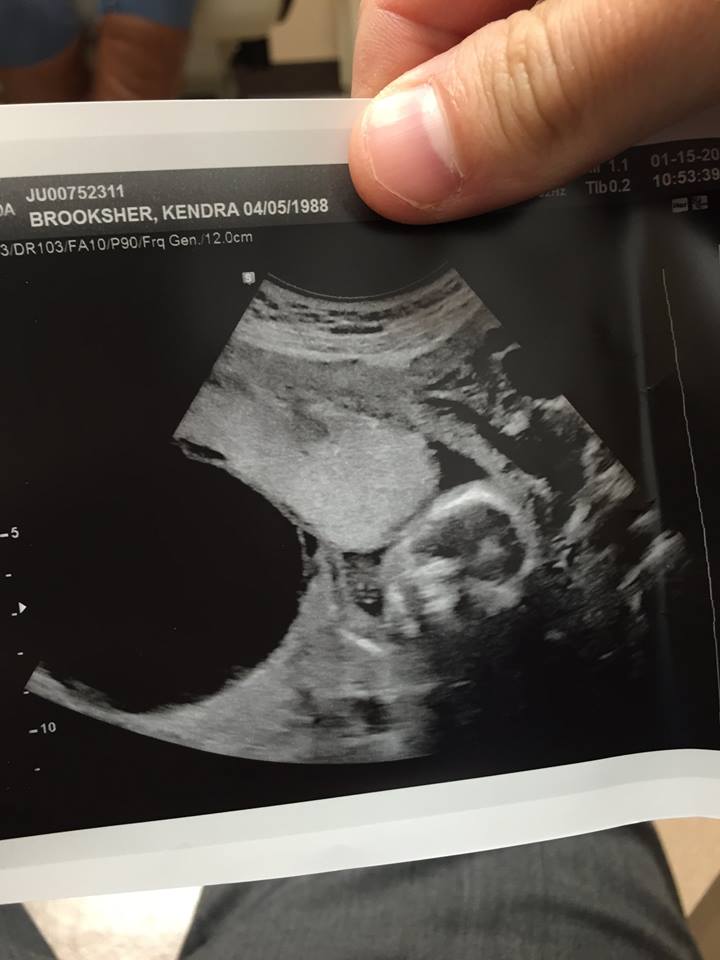

On December 16th 2014, Matt & Kendra's world was turned upside down when they discovered a problem with their unborn baby via ultrasound. It has been a very long journey in such a short amount of time. After many emotional diagnosis that changed from day to day and being told that their baby (Samuel) would not make it past 17 weeks in the womb, they discovered that he has a rare phenomenon called a posterial urethral valve obstruction. Severe cases such as Samuel's can lead to renal and respiratory failure from lung underdevelopment as result of low amniotic fluid volumes, requiring intensive care and close monitoring. In this case, life threatening damage had already been done. Samuel's obstruction was very severe which resulted in his bladder expanding 4-5 times what it should be. The photo below shows his bladder (empty black space to the left) compared to his head (right).